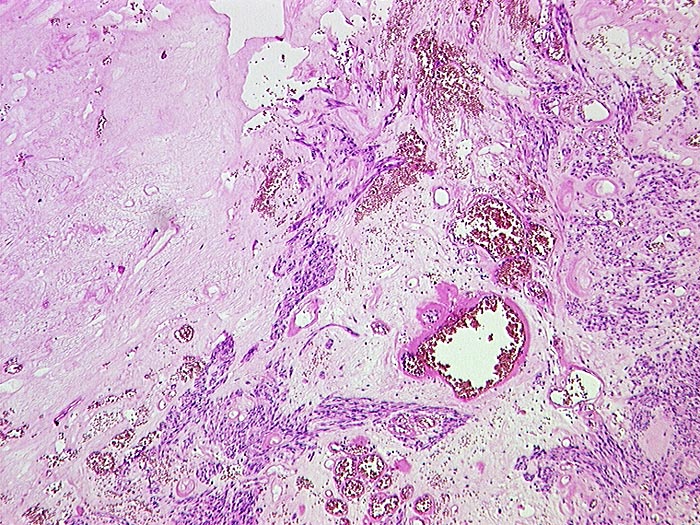

Makroskopisch imponieren kleine Tumoren als peritoneale, intramurale oder submuköse Knoten. Grössere Tumoren wölben sich oft vor und können ulzerieren. Die Schnittfläche ist weisslich und kann Einblutungen, Zysten, Fibroseareale oder Nekrosen aufweisen. Histologisch werden Spindelzelltyp (70%), Epitheloidzelltyp (20%) oder gemischtzelliger Typ (10%) unterschieden. Der histologische Subtyp scheint keinen Zusammenhang mit zugrundeliegender Mutation, Therapieansprechen und Prognose zu haben. Gelegentlich sind vor allem die kleineren Tumoren zellarm und kollagenreich.

• Der Tumor besteht aus längs und quer getroffenen Faszikeln spindelförmiger Tumorzellen, welche an glatte Muskelzellen oder Schwannzellen erinnern.

• Herdförmig pseudozystische Auflockerung des Tumorgewebes.